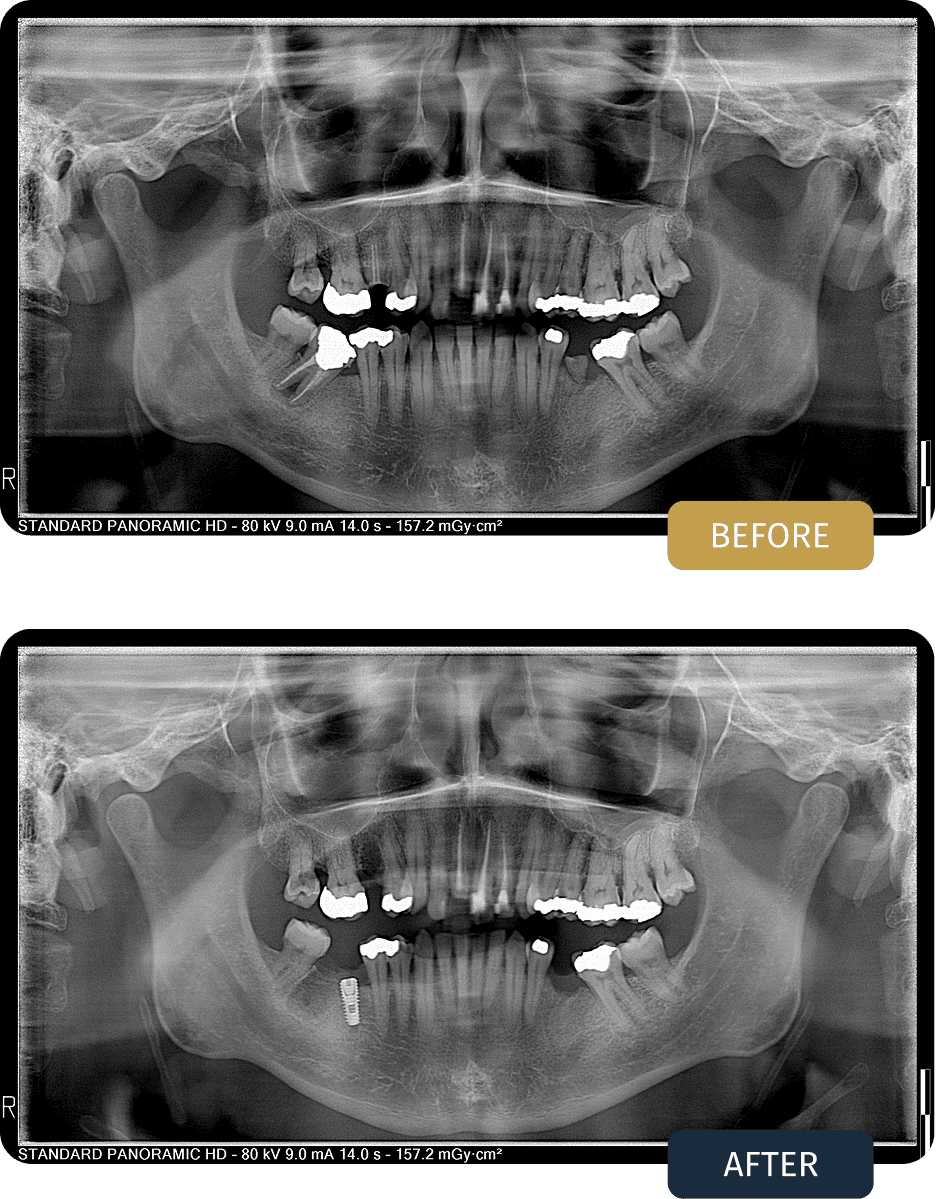

Panoramic imaging revealed widespread restorative needs across both arches, including non restorable teeth requiring extraction and areas where long term support would not be possible without implant placement.

Post treatment panoramic imaging confirmed successful implant placement, stable restorations, and a balanced occlusion across both arches.